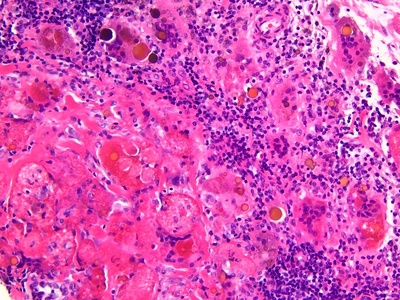

Acute inflammation

Rapid, short-lived immune response to injury or microbes that brings neutrophils and fluid to tissues. Occurs in skin, lungs, gut, joints. Causes obvious local signs; seek care for severe pain, spreading redness, high fever, or systemic symptoms.

Suppurative (purulent) inflammation

Inflammation dominated by pus formation (neutrophils and dead tissue), commonly causing abscesses or cellulitis. Found in skin, soft tissue, organs. Often requires drainage and antibiotics; seek urgent care for spreading redness or systemic illness.

Neutrophilic inflammation

Inflammation characterized by neutrophil influx, typical of acute bacterial infections and early injury. Produces pus and acute symptoms. Rapid progression, systemic signs, or failure to improve requires prompt medical attention.